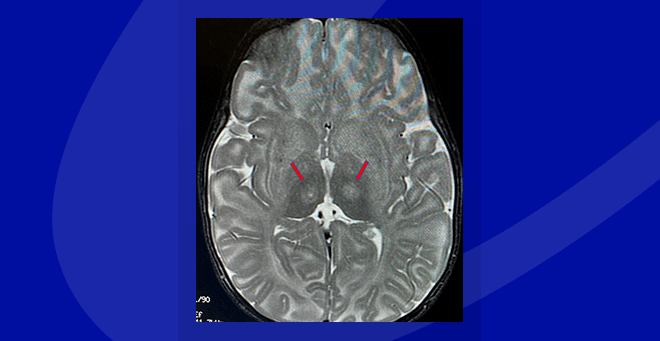

• Innovative neurosurgical technique used in Tay-Sachs gene therapy clinical trial

Innovative neurosurgical technique used in Tay-Sachs gene therapy clinical trial

Oguz Cataltepe, MD, describes the innovative neurosurgical procedure used to treat patients in the new clinical trial for a gene therapy targeting infantile Tay-Sachs and Sandhoff diseases.